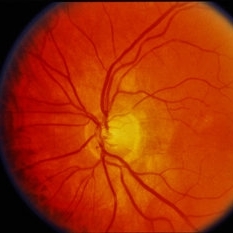

Age Related Macular Degeneration

Age Related Macular Degeneration

Mar 29 2013 by Henry J. Kaplan, MD

Geographic atrophy with small hemorrhages due to subretinal neovascular membrane development.

Condition/keywords: choroidal neovascularization (CNV), geographic atrophy